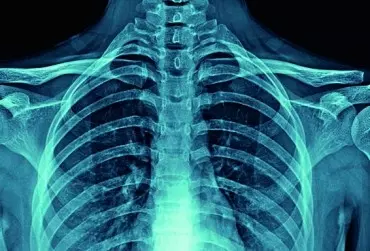

Promieniowanie RTG w praktyce fizjoterapeutycznej

Promieniowanie radiologiczne (RTG) jest złotym standardem diagnostyki obrazowej. Jest badaniem szybkim w wykonaniu, powszechnym i niedrogim, a ukazanie rzeczywistego obrazu układu kostnego daje mu atut, którym przewyższa nowoczesne badania diagnostyczne. Zastosowanie zarówno aparatów rentgenowskich, jak i innych diagnostycznych aparatów nieinwazyjnych ma swoje zasady, cele i wzajemnie się uzupełnia. Należy pamiętać, w jakich sytuacjach ich używać, aby wykluczyć czynnik szkodliwości w dojściu do celu, jakim jest diagnostyka pacjenta.